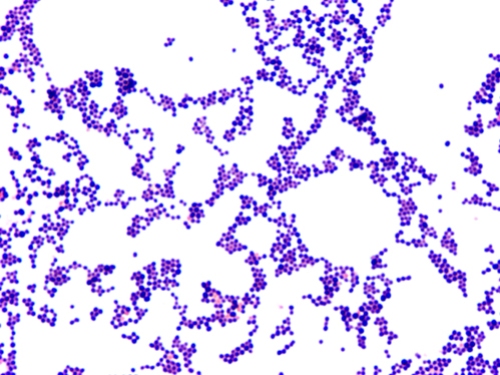

Gram pos cocci

This is an example of a Gram pos cocci (Staphylococcus epidermidis)

This photo demonstrates almost all arrangements - pairs, clusters, tetrads, singles, and even a chain or two. Since there is no real majority, a cellular arrangement would not reported. Also, the occurrence of one or two chains is probably by chance as the cells were being spread onto the slide.

Gram stain report: 4+ G pos cocci